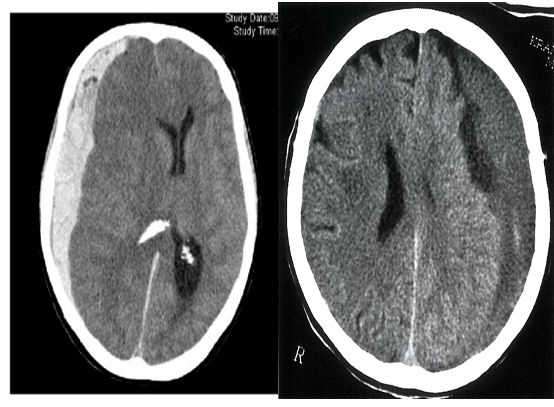

- Acute-on-chronic SDH: hyperdense areas (recent hemorrhage) admixed with isodense or hypodense areas (older hematoma)

Acute on chronic subdural hematoma